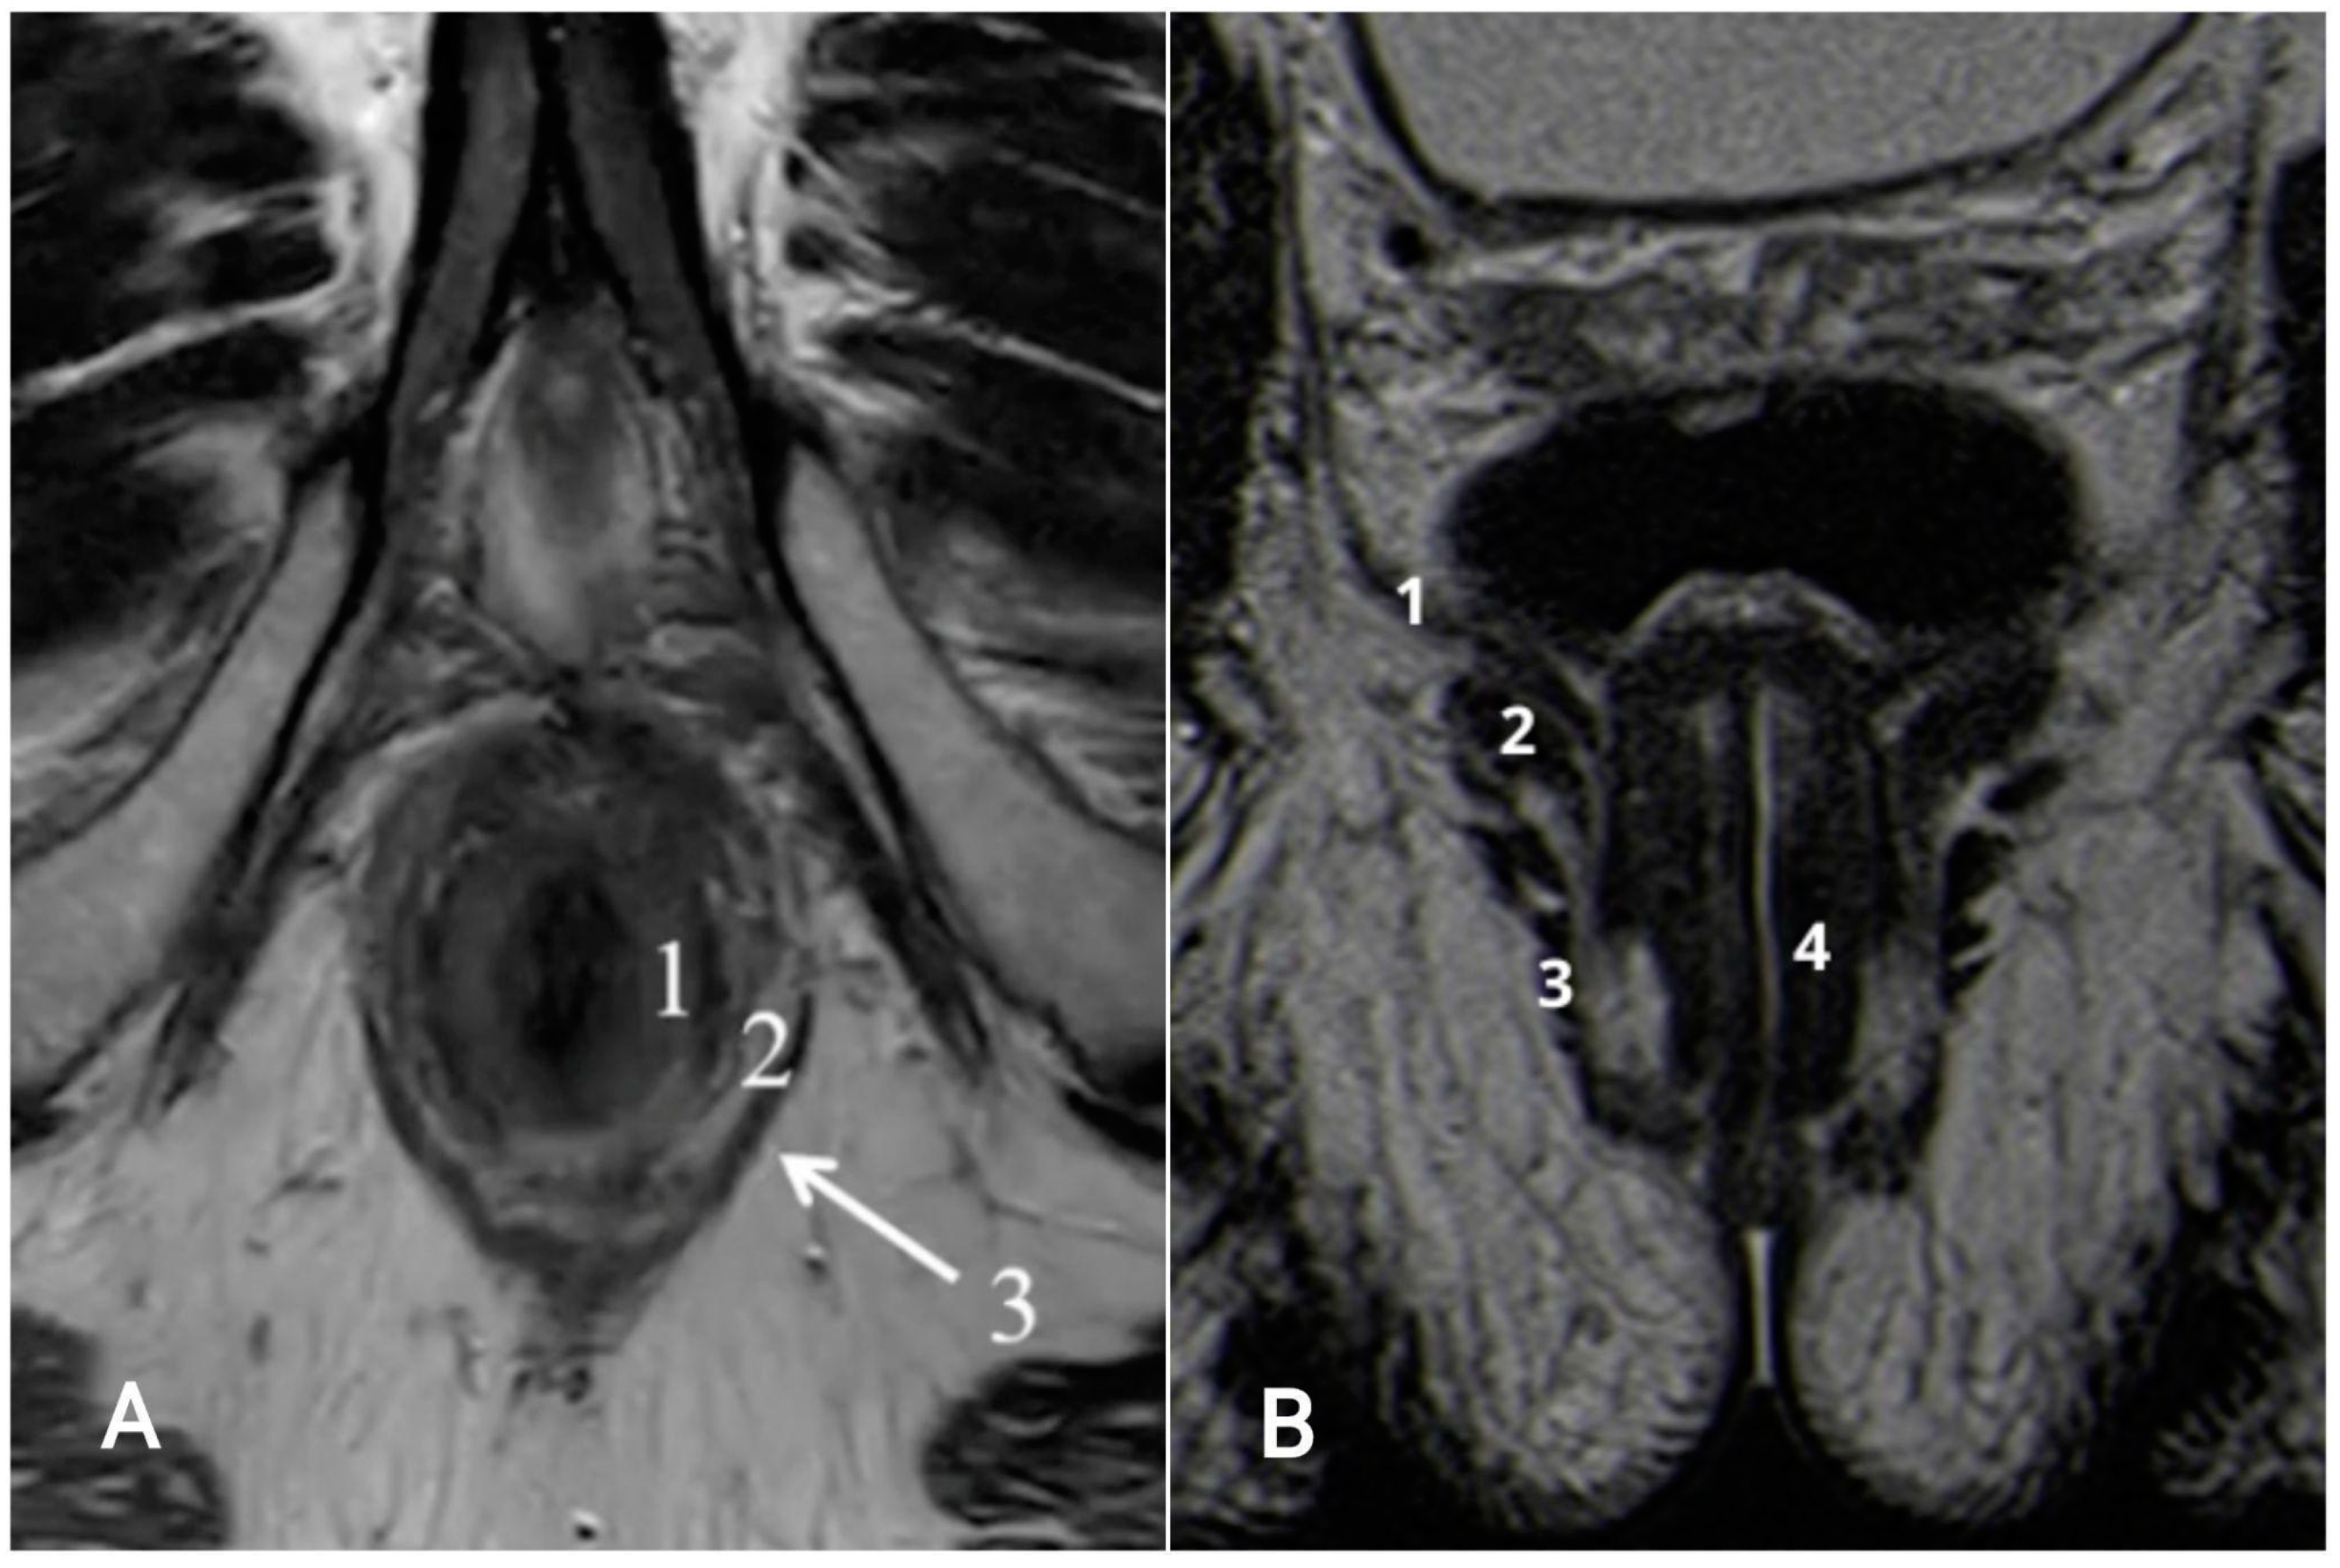

4. Anatomy of the Anal Canal Location

7.1. T-Staging